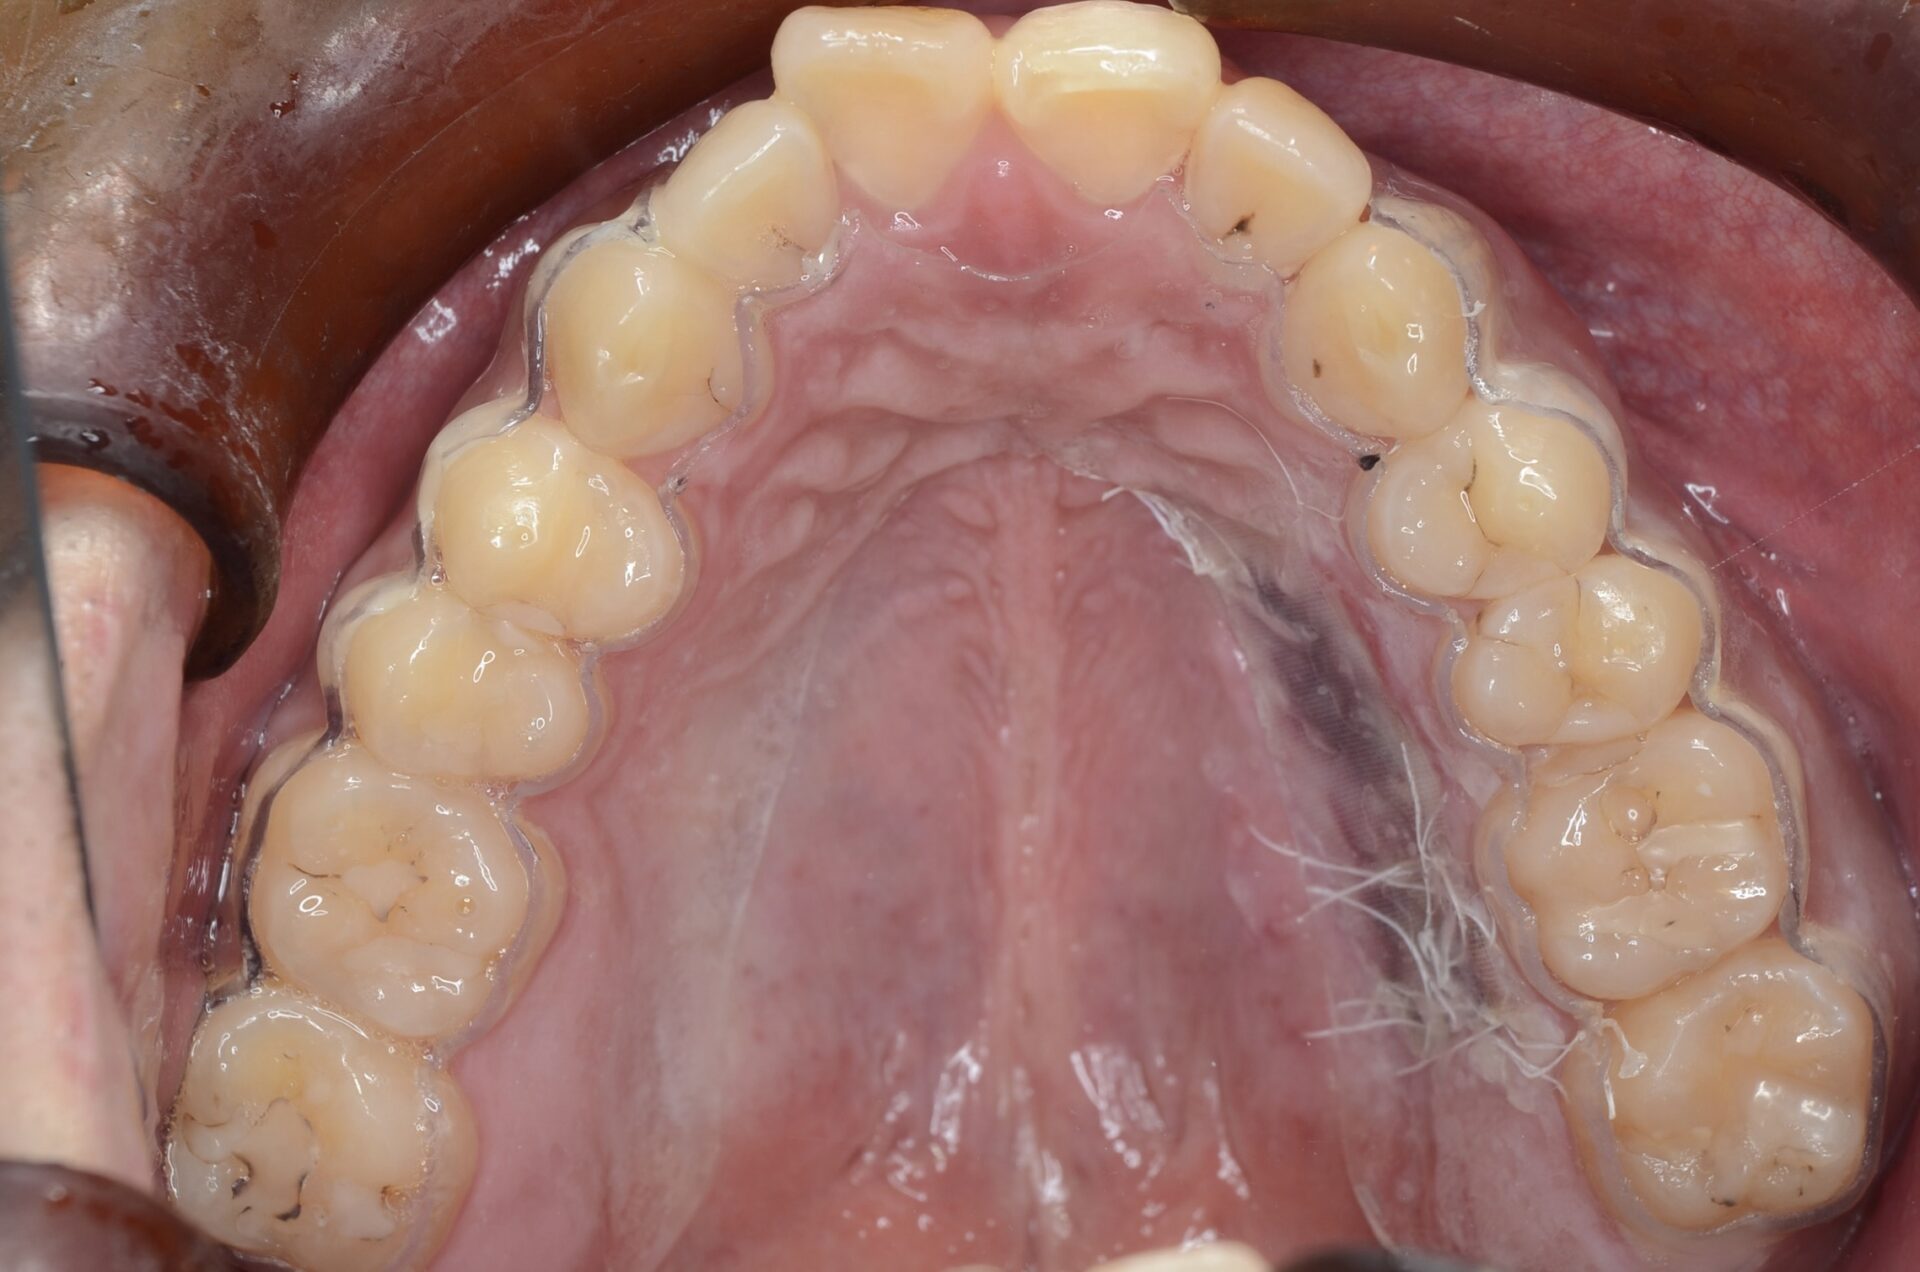

保護用マウスピース

口蓋部を保護するマウスピースを用意しています。これを使うと、傷の治りが2倍早い印象です。 -